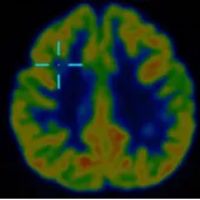

借助医院先进的高清晰度、高对比度薄层扫描核磁共振,配合PET-CT检查,终于在右额叶发现了一个极其微小的致痫病灶。这个位置,与脑电图提示、以及临床发作特征完美吻合。更幸运的是,虽然病灶位置深,但范围很小。